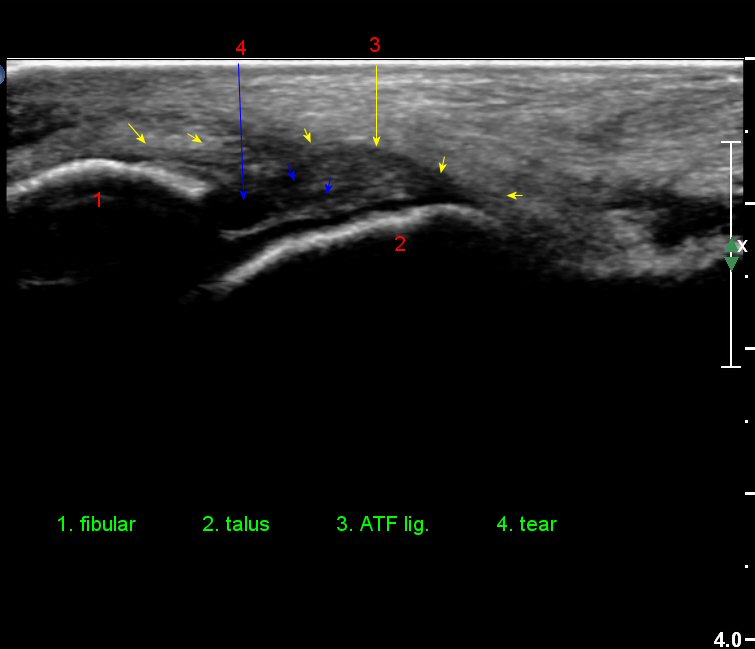

Àü°ÅºñÀδë Á¾´Ü¸é°Ë»ç¿¡¼­ ¾È´ë ºñ°ñ ºÎÂøºÎÀÇ Àú¿¡ÄÚ ºÎÁ¾°ú ºÎºÐÆÄ¿­ÀÌ °üÂûµÈ´Ù(»çÁø 4).

Àü°ÅºñÀδë Á¾´Ü¸é°Ë»ç¿¡¼­  Àú¿¡ÄÚ ºÎÁ¾ÀÌ °¨¼ÒÇϰí ÀδëÀÇ ¿¡ÄÚ°¡ Áõ°¡µÇ¾ú´Ù(»çÁø 2, 3, 4).